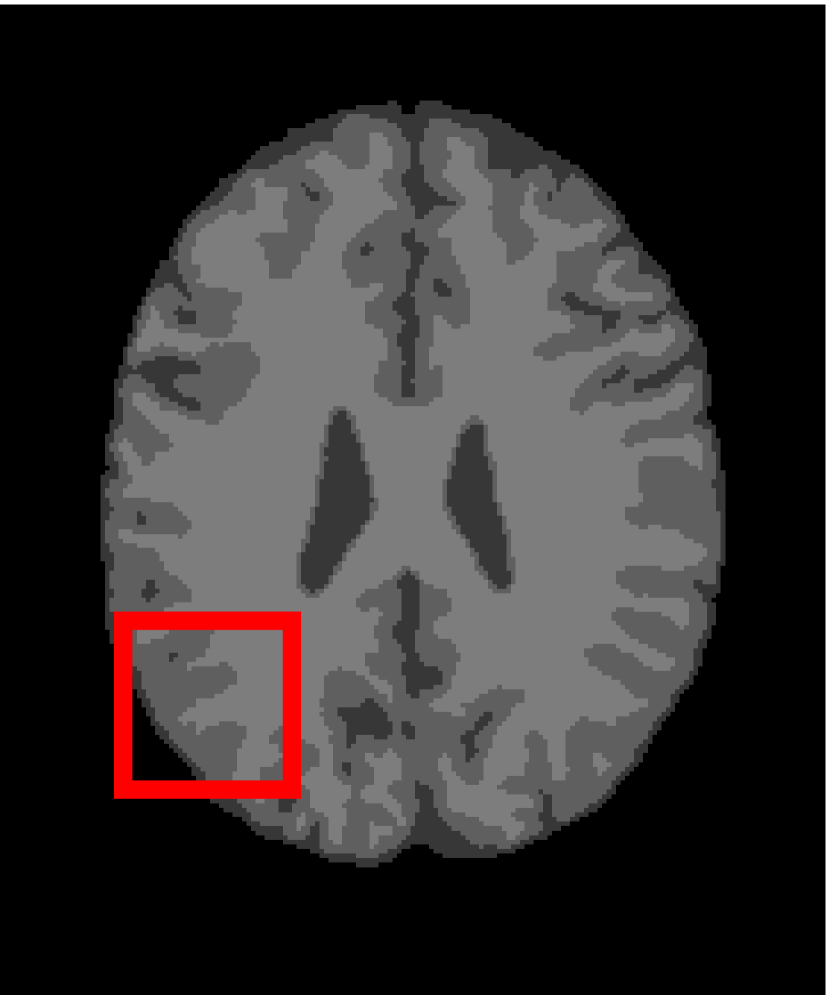

In the second experiments, we segment two medical images coming from a simulated brain database (BrianWeb): http://www.bic.mni.mcgill.ca/brainweb/. The two images are generated by T1 modality with slice thickness of 1mm resolution, 9% noise and 20% intensity non-uniformity. Here, the two images are represented two slices in the axial plane with the sequence of 100 and 110. Moreover, there are golden standard segmentations in the dataset. We set the numbers of clusters to 4. The visual comparisons are illustrated in Figs. 6 and 7.

Figure 7: Segmentation results for the second medical image. From (a) to (l): ground truth, noisy image and results of FCM_S1, FCM_S2, FGFCM, FLICM, KWFLICM, ARKFCM, FRFCM, WFCM, DSFCM_N, and LRFCM.

By focusing on the marked red square in Figs. 6 and 7, we easily find that FCM_S1, FCM_S2, FGFCM and ARKFCM are sensitive to noise. FLICM and KWFLICM are vulnerable to severe intensity inhomogeneity. FRFCM brings overly smooth results due to the use of gray level histograms. WFCM and DSFCM_N cause several contours to change. However, LRFCM acquires clear contours and suppresses noise adequately. Moreover, we find that the segmentation result of LRFCM is closer to ground truth.